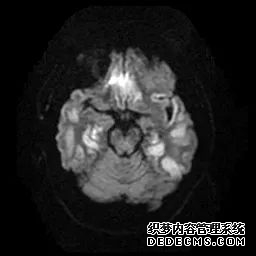

脑MRI显示尾状核、扁豆状核和脑梗头部T2/FLAIR呈双侧对称异常高信号。扩散限制涉及这些区域,其特征是扩散加权DWI(B-1000)上的高强度,ADC图上相应的减弱强度。

低血糖性脑病是一种代谢性脑病,它是由脑细胞对葡萄糖的供应和使用之间的不平衡引起的。脑MRI,尤其是DWI是诊断和预测该病预后的重要工具。

这个病例说明了低血糖脑病,有典型的病史和血液指标,结合MRI表现,DWI为诊断提供了最好的线索。